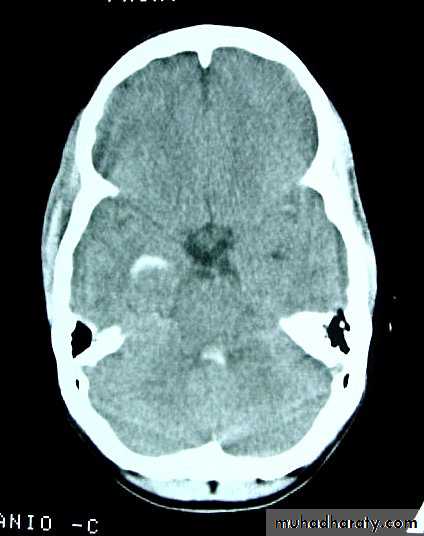

c. Intracerebral Haematoma

This is the least common of traumatic haematoma.They are due to areas of traumatic contusion coalescing into a contusional haematoma.

Disrupted cerebral tissue release thromboplastins that potentiate haemorrhage.

CT scan: appear as hyperdence lesions with associated mass effect and midline shift.Large intracerebral haematomas should be evacuated unless the patient’s neurological state is improving.

Small inracerebral haematomas may not require removal, but be aware that they can expand.